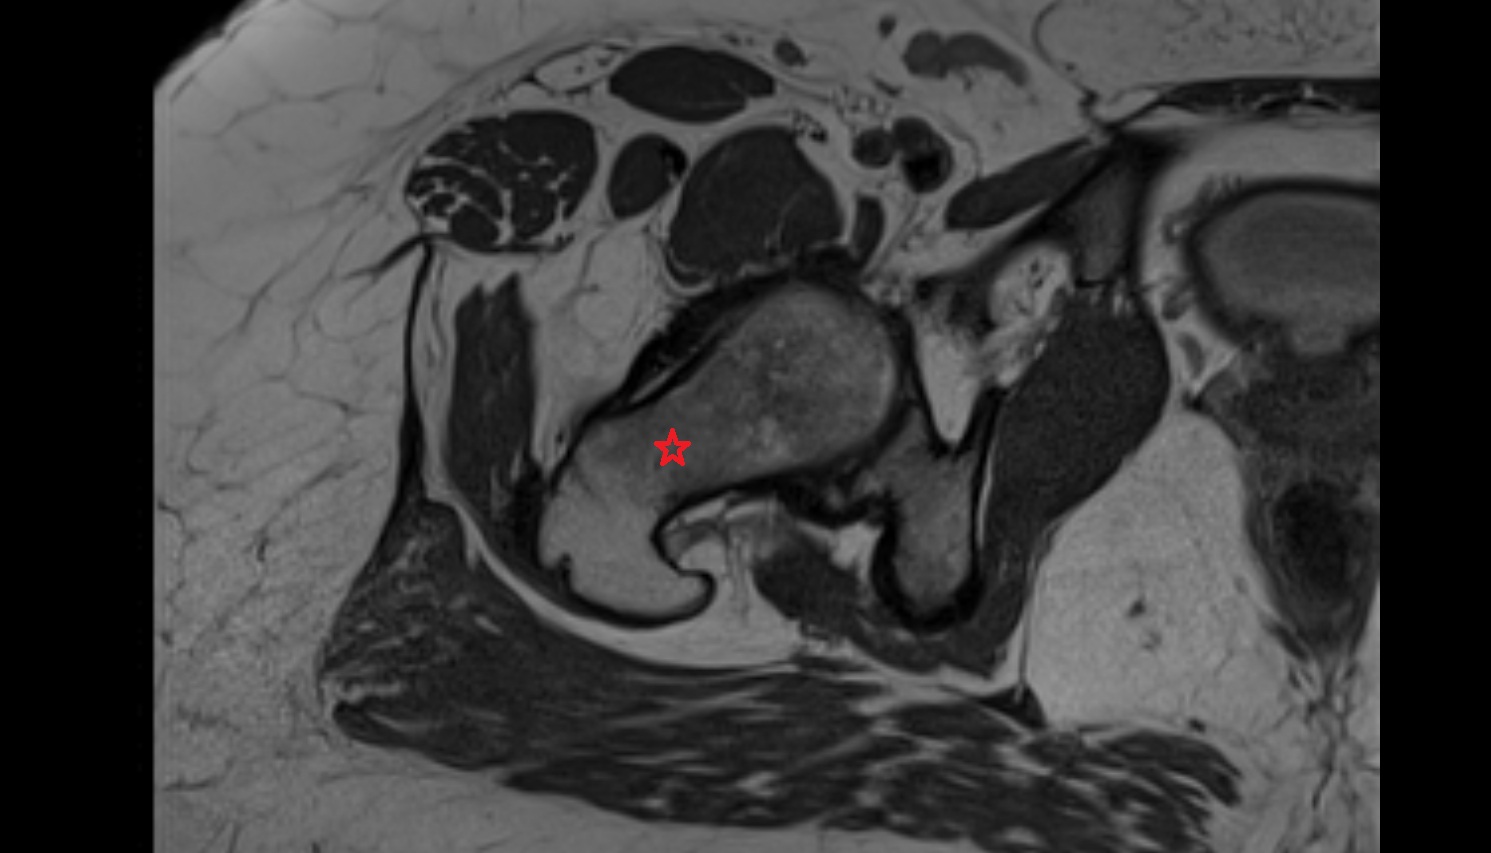

- Uterus

- Body of uterus

- Fundus of uterus

- Cervix of uterus

- Isthmus of uterus

- Vagina

- Endometrium of uterus

- Myometrium of uterus

- Perimetrium of uterus

- Junctional zone of uterus